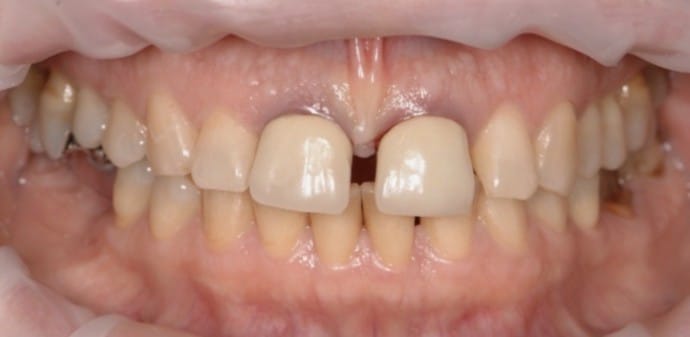

Na bezplatnej konzultácii vám navrhneme plán liečenia. Obyčajne sa na zuby, ktoré sú poškodené viac ako 40%, odporúča náhrada pomocou moderných keramických faziet alebo zirkónových koruniek, ktoré majú oproti kompozitným výplniam množstvo výhod - pevnosť, estetika a trvanlivosť!

- Estetika - farba a priesvitnosť je prispôsobená sklovine Vašich zubov, preto sú zirkónové korunky vizuálne na nerozoznanie od vlastných zubov.